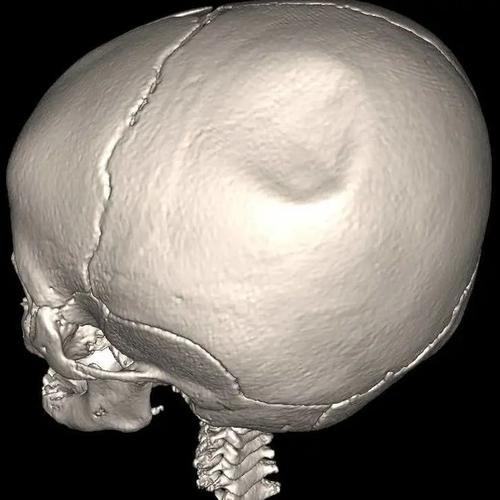

(图片来源网络,侵删)

(图片来源网络,侵删)- 脊髓问题: 如脊髓脊膜膨出等。